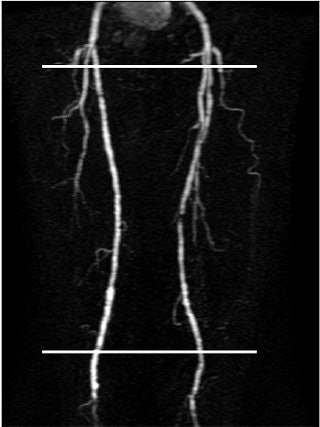

![]() |

| White lines indicate sites of cine phase contrast flow volume measurements. |

The mean peak flow velocity above/below lesion was significantly higher in the segments with severe disease (1.9) or occlusion (1.4) versus normal segments (1.4). In addition, a delay in peak velocity below lesions showed significant positive correlation with lesion severity, the authors stated in their abstract.

The mean flow volume above/below lesions was 3.9 in occluded vessels and 2.3 in normal volunteers. The group found that flow curves tended to change from triphasic to biphasic or monophasic below moderate to severe stenoses (21 of 35) and occlusions (33 of 35).